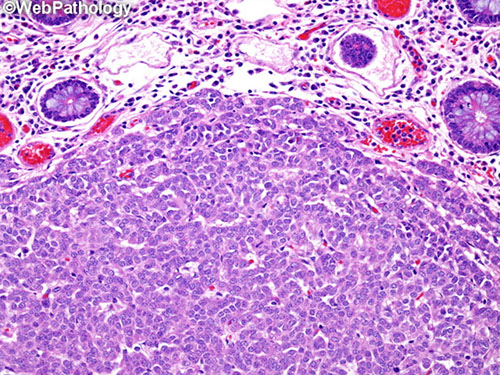

Intro to biopsy

- reactive changes can be overlaying ca that was too deep to bx

- superficial portions of WDNT can be subtle, usually not assoc c inflam dz (as in the stomach)

- mets can mimic intraepithelial stuff if spread along sm intestine surface

- Pancreatic lesions can mimic sm bowel lesions when they arise from the ampulla

- must screen dilated lacteals for isolated cancer cells (mets MC from breast, lug, melanoma, and sometimes mesothelioma

- prominent crushed Brunner glands can look like neural tumors; but can avoid misdiagnosis by ordering PAS

- duodenum, and ampullary region are prone to reparative changes that can look like adenoma